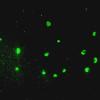

Neuronal Ceroid Lipofuscinosis (NCL) (5)